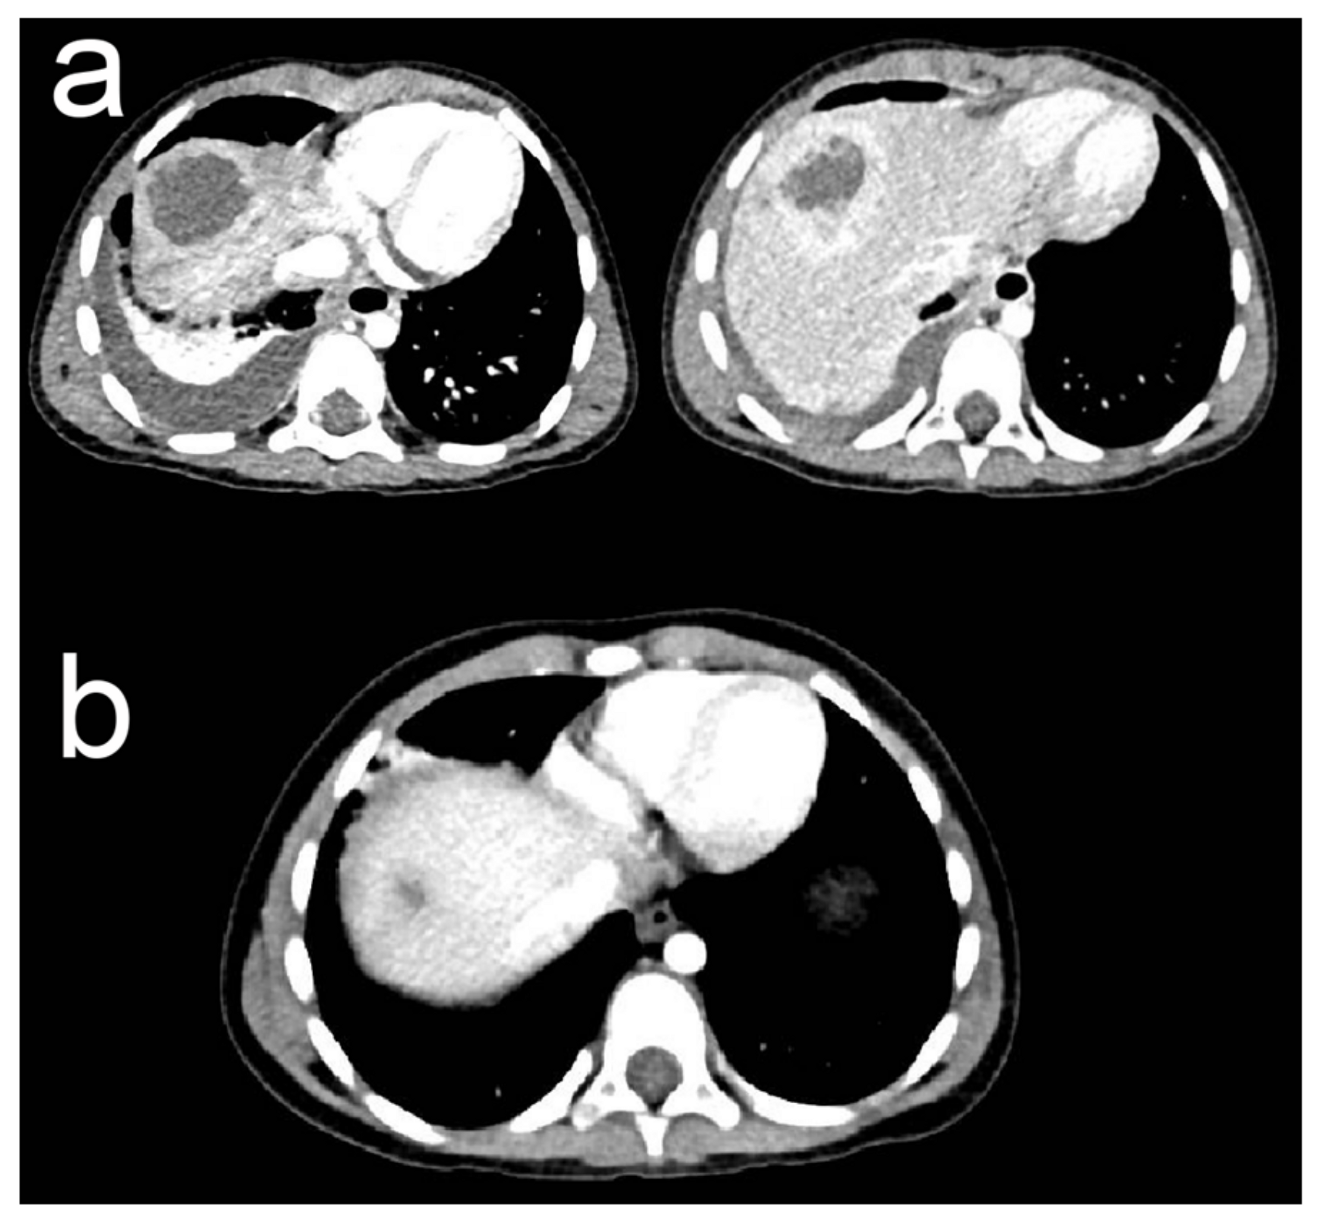

2. Case Presentation